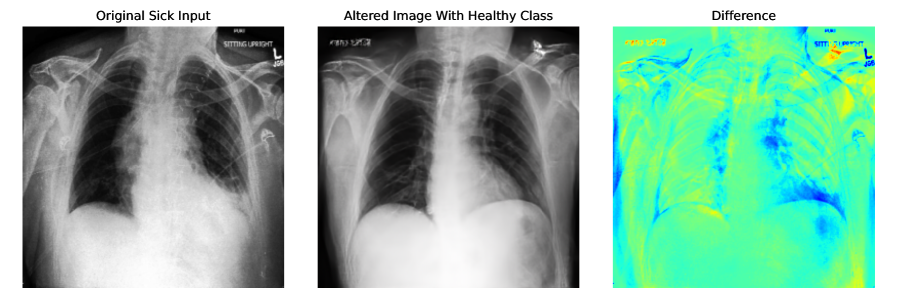

Appendix E More Explainability Results

More explainability results can be found in Figure 6, and Figure 7. Input sick images have been altered to healthy class by adding noise to the input image and denoising with the healthy class. For CheXpert t=0.5 and for ISIC t=0.3 are used. CFG scale is 7.5.

Refer to caption

Figure 6: More explainability results for CheXpert by converting input sick images to healthy images. t=0.5 and CFG=7.5 are used for generating these images.